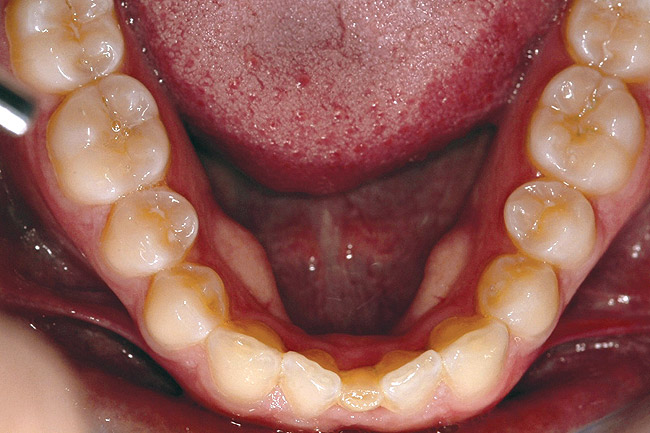

Fig 21 (and Fig 20). There is significant lateral dentoalveolar expansion of arches and alveoloskeletal correction in maxillary and mandibular anterior regions. Alveolar bone volume was increased in lower anterior to create optimal implant sites and establish ideal interincisal function and stability.

Figure 21

Fig 18 (through Fig 21). Note lack of alveolar development from congenitally missing Nos. 24 and 25. Surgical procedures after 5 months of orthodontic alignment included single-tooth osteotomies Nos. 6 to 11 and Nos. 21 to 28 and buccal corticotomies on all other teeth. Anchorage plate was stabilized to piriform rim.

Figure 18